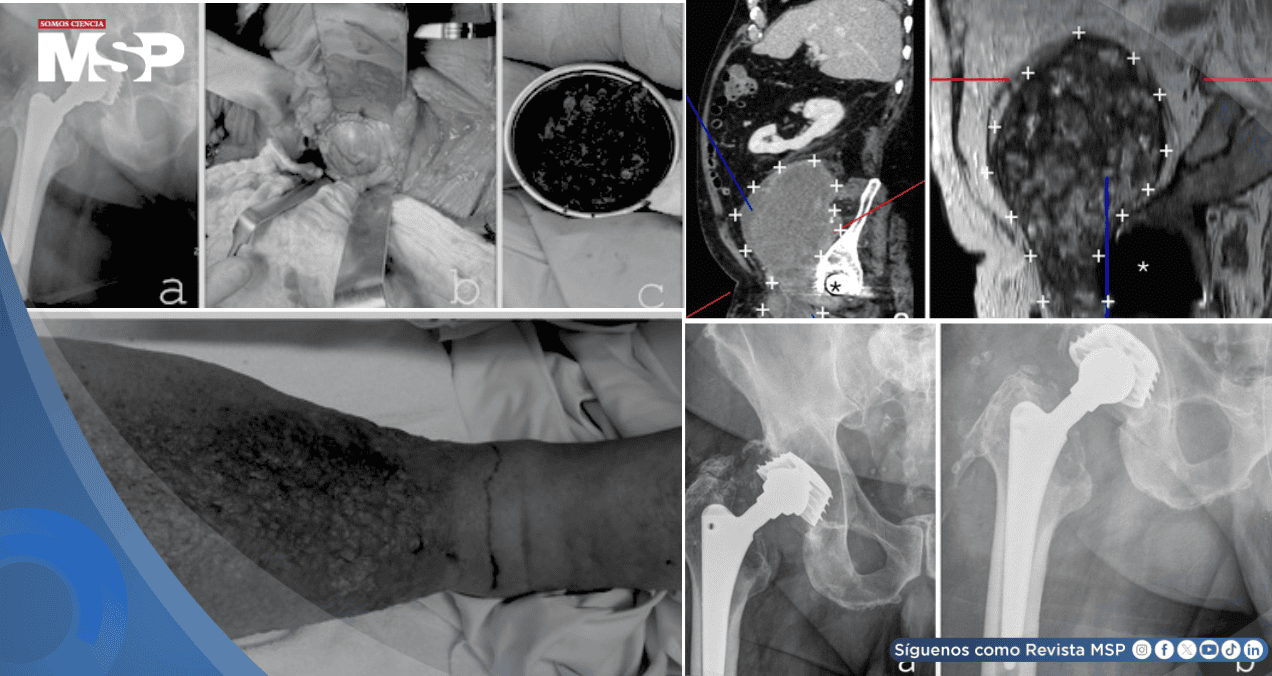

La lesión, de más de 15 cm, tenía aspecto complejo y estaba adherida a importantes vasos sanguíneos, por lo que se sospechó inicialmente de un tumor maligno. El paciente llegó tras un año de hinchazón progresiva y severa en su pierna derecha, que había evolucionado a una elefantiasis (engrosamiento extremo de la piel y tejidos), y tras haber sido tratado previamente por una infección en la piel (erisipela).

Al analizar las imágenes con más detalle, se observó una relación anatómica muy estrecha entre la masa "tumoral" y la antigua articulación de la cadera protésica. Esto hizo reconsiderar el diagnóstico.

Se realizó una punción de la cadera, cuyos resultados no fueron concluyentes, en parte por la posible interferencia de los residuos metálicos. Frente a la sospecha de que se trataba de una reacción adversa local al desgaste de la prótesis (una complicación conocida pero poco frecuente que puede formar masas o pseudotumores), y no de un cáncer, los médicos decidieron intervenir.

La cirugía se realizó con dos equipos: uno para extirpar la masa principal (dejando un pequeño resto por seguridad, al estar adherida a vasos) y otro para revisar la prótesis de cadera. El análisis inmediato de la masa durante la operación no mostró células cancerosas.

Dentro de la articulación, se encontraron signos de corrosión en la unión de la cabeza metálica con el vástago. Dado que el vástago principal estaba bien fijado al hueso, lo preservaron, pero reemplazaron toda la parte acetabular (la copa) y la cabeza femoral por componentes modernos de cerámica y polietileno especial para mayor durabilidad.

El estudio definitivo del tejido extirpado confirmó que era un seudotumor: una masa formada por una reacción inflamatoria crónica a partículas microscópicas de metal y plástico del desgaste de la prótesis, mezclada con sangre antigua organizada.

No había tumor maligno. Tras la cirugía, la hinchazón de la pierna mejoró notablemente al liberarse la compresión vascular. Sin embargo, se identificó una infección profunda de la prótesis por una bacteria resistente (SARM), que no se había detectado en las pruebas previas.